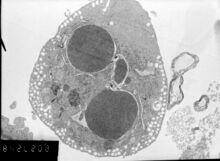

- Chromatin undergoes condensation into compact patches against the nuclear envelope (also known as the perinuclear envelope) in a process known as pyknosis, a hallmark of apoptosis.[54][55]

- The nuclear envelope becomes discontinuous and the DNA inside it is fragmented in a process referred to as karyorrhexis. The nucleus breaks into several discrete chromatin bodies or nucleosomal units due to the degradation of DNA.[56]

Apoptosis progresses quickly and its products are quickly removed, making it difficult to detect or visualize on classical histology sections. During karyorrhexis, endonuclease activation leaves short DNA fragments, regularly spaced in size. These give a characteristic "laddered" appearance on agar gel after electrophoresis.[57] Tests for DNA laddering differentiate apoptosis from ischemic or toxic cell death.[58]